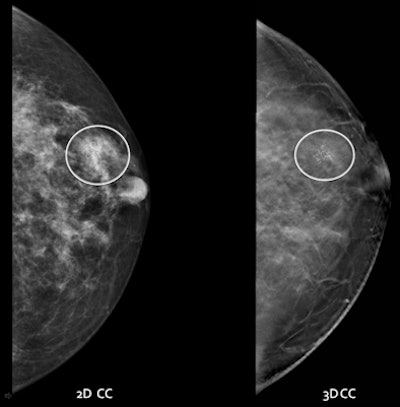

![]() |

| Digital mammography and DBT, craniocaudal view. Images courtesy of Dr. Stamatia Destounis. |